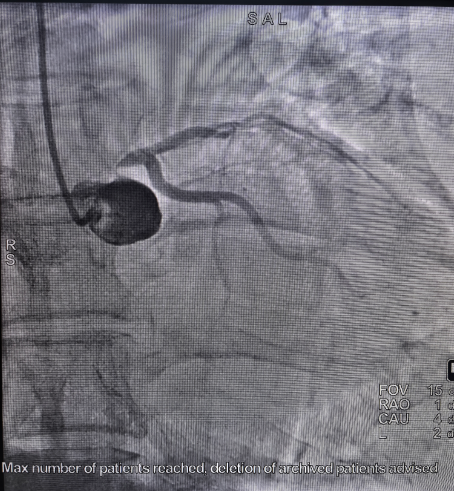

这场抢救不仅是一次本能的职业反应,更是一场依托于日常严格训练、高效协同的应急实战。当天晚间,心血管介入团队罗超、王忠颖医生为患者紧急实施冠状动脉造影。结果显示,患者冠状动脉左主干严重病变,狭窄程度高达99%,残余管腔细如发丝。

△术前术后

左主干被称为心脏的“生命线”,承载着70%以上的心肌供血,术中一旦闭塞将危及生命,手术风险极高。介入团队果断决策,采用高难度的冠脉介入导丝飘入技术:将导丝头端预塑为特定弯形,脱离指引导管支撑,依靠血流动力与导丝弹性,“漂浮”进入极度狭窄的血管。最终,手术成功实施,闭塞血管被顺利开通。